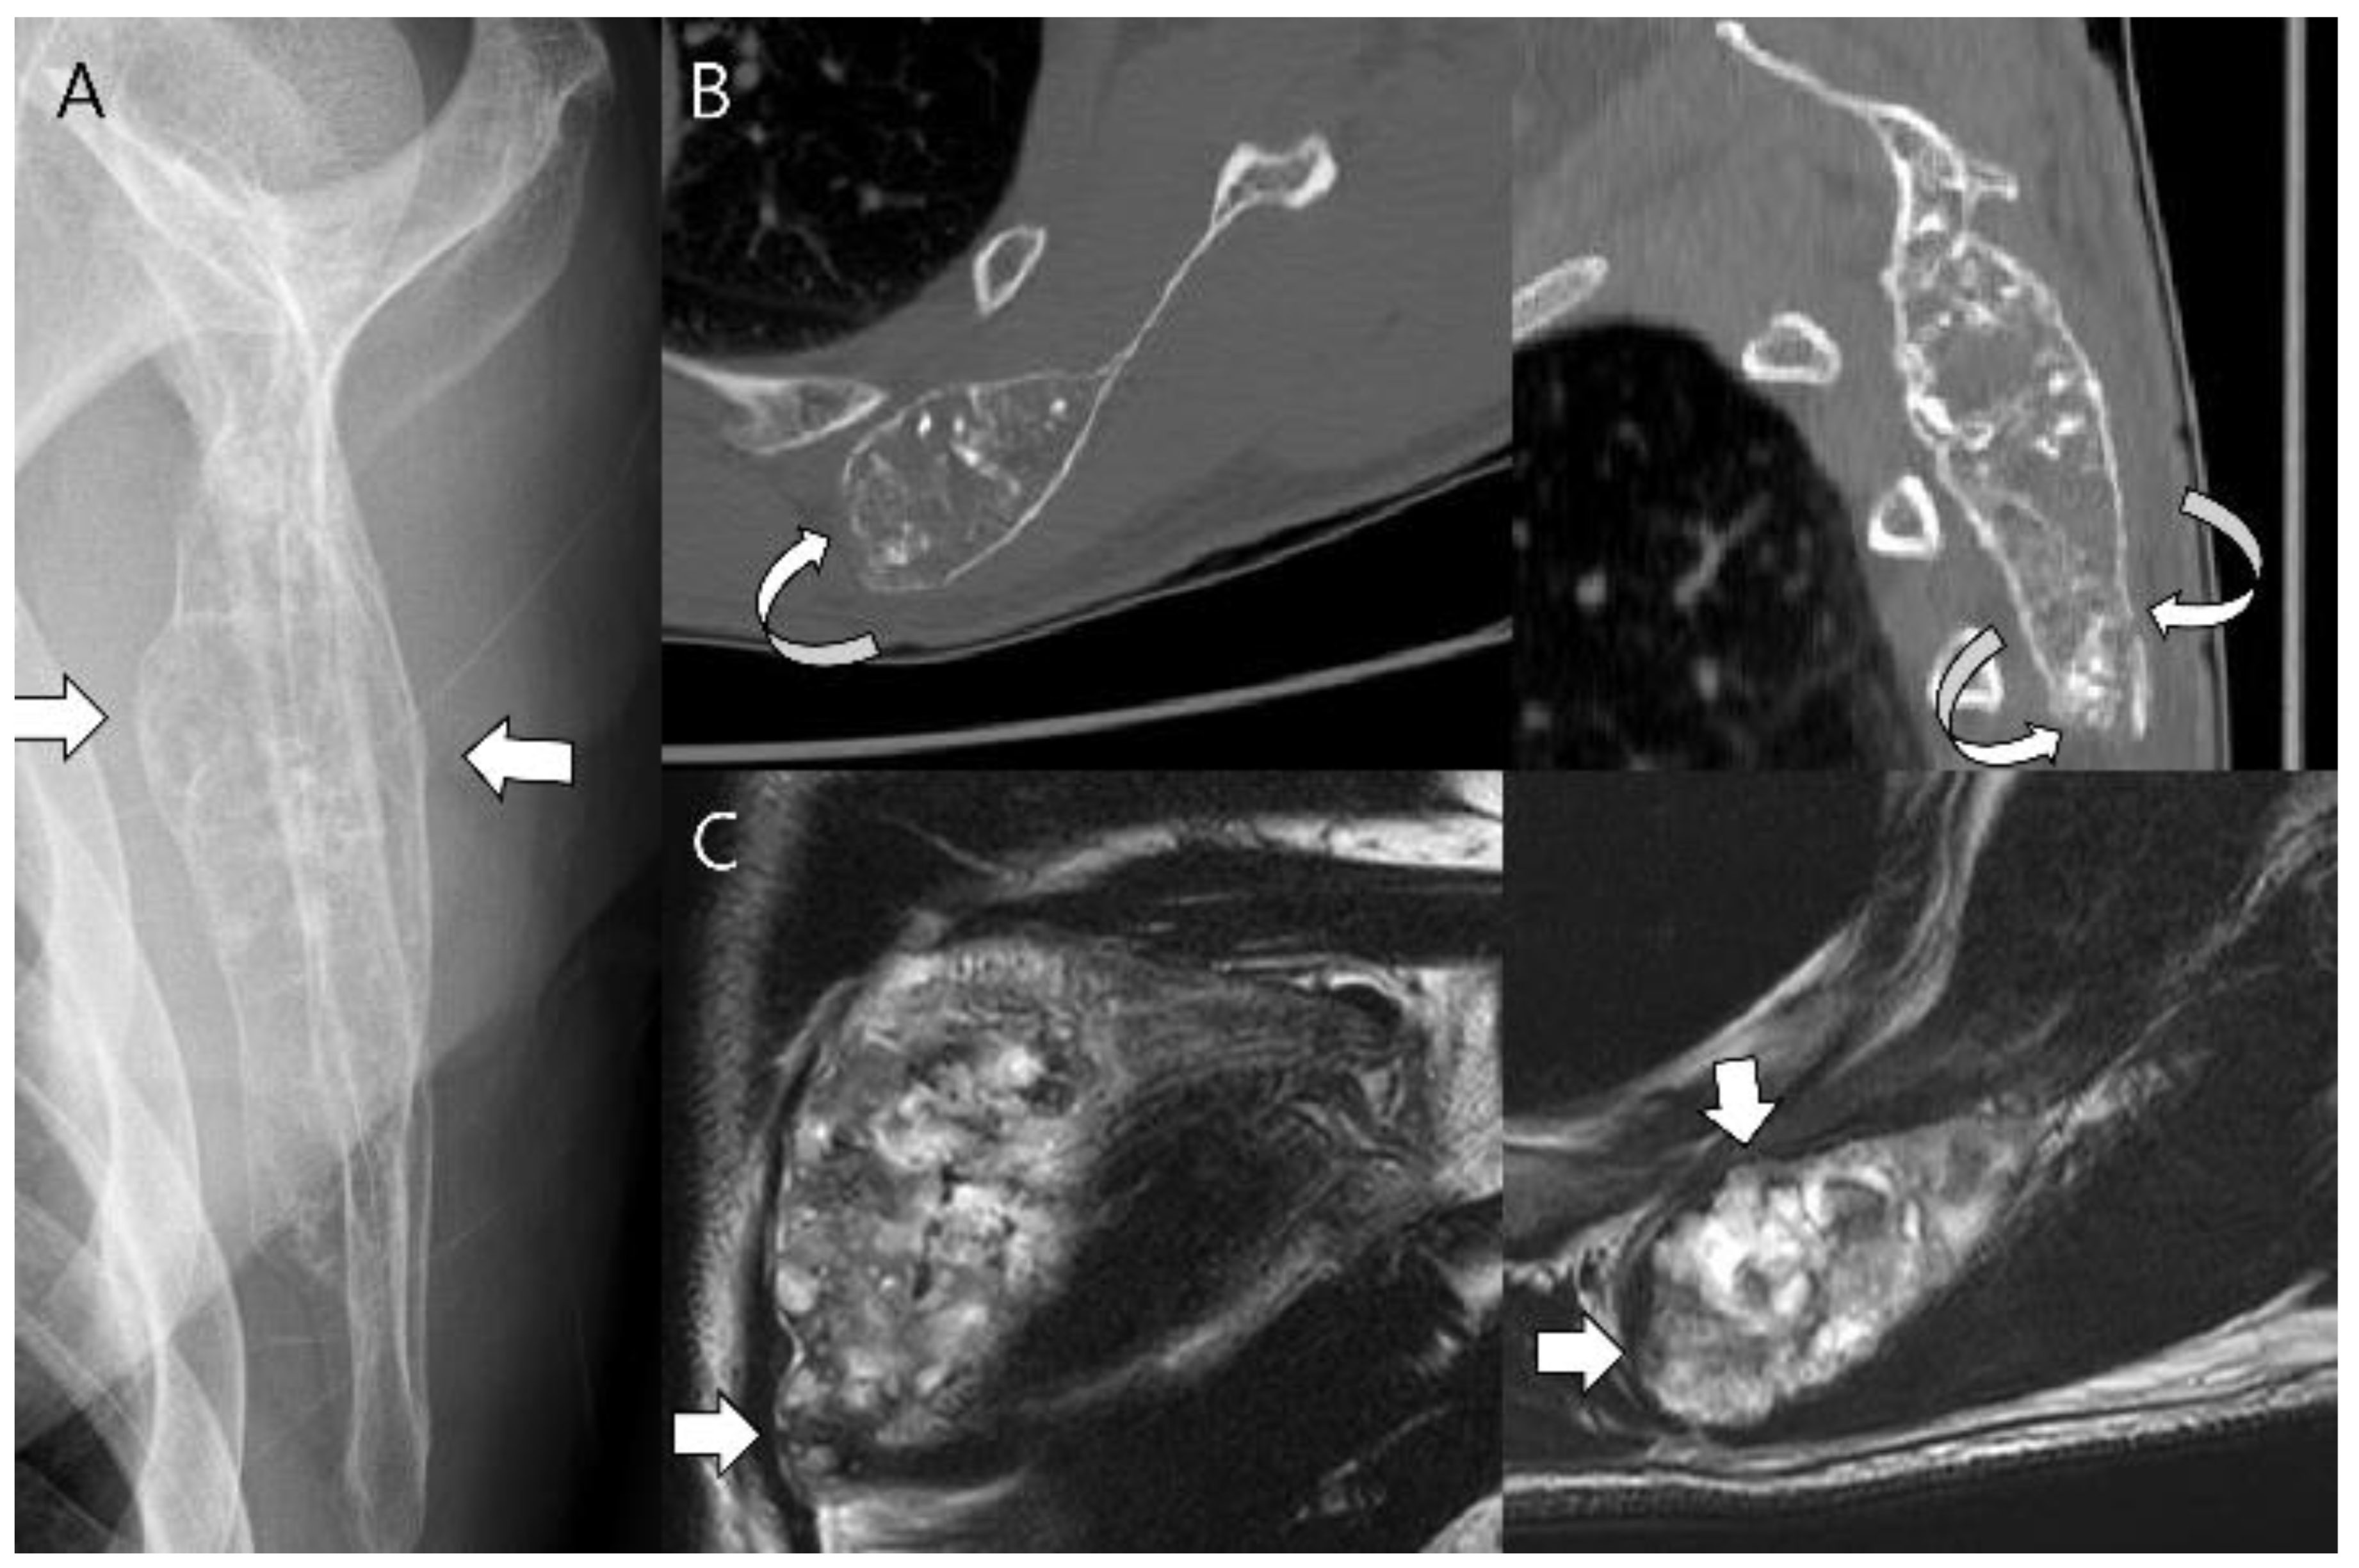

- Norman, A.; Sissons, H.A. Radiographic hallmarks of peripheral chondrosarcoma. Radiology 1984, 151, 589–596. [Google Scholar] [CrossRef] [PubMed]

- Bernard, S.A.; Murphey, M.D.; Flemming, D.J.; Kransdorf, M.J. Improved differentiation of benign osteochondromas from secondary chondrosarcomas with standardized measurement of cartilage cap at CT and MR imaging. Radiology 2010, 255, 857–865. [Google Scholar] [CrossRef]